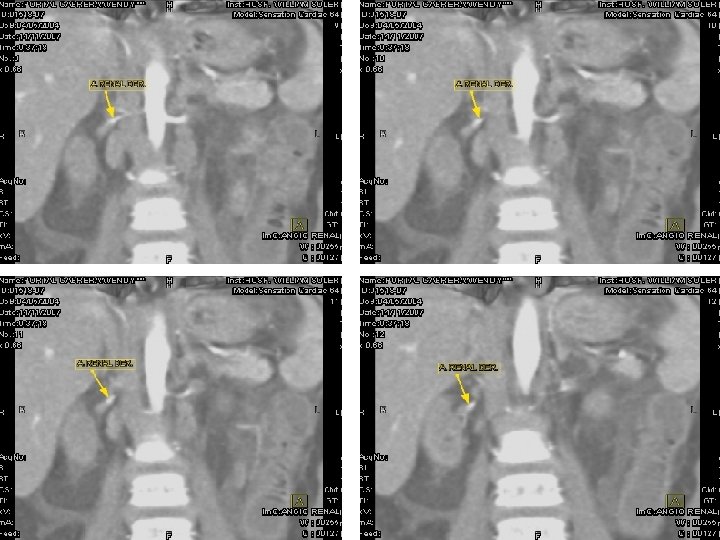

En un estudio de Angiotac Renal contrastada no se observaron zonas de estenosis vasculares llamando la atención el afinamiento de las arterias renales a su entrada a los hilios con escasa captación y excreción del contraste en ambos órganos. Durante la evolución posterior la paciente ha presentado episodios de Peritonitis, cuadros de descompensación cardiovascular relacionados con Pericarditis con efusión y notable hipertrofia miocárdica, especialmente de cavidades izquierdas relacionada con su hipertensión sostenida. Actualmente se encuentra bajo tratamiento de hemodiálisis crónica a la espera de Trasplante Renal.

ANGIOTAC